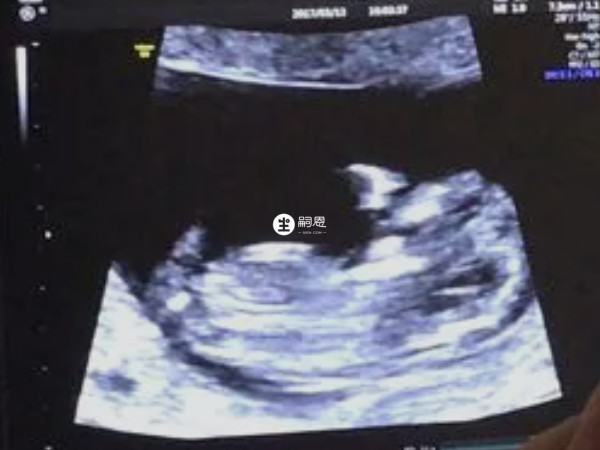

在NT影象中,可能會出現類似於線條的東西,可以看到圖上這樣比較明顯的線條有三條,有的時候B超看到的是一條線,而這個大概率就是女寶寶的外生殖器官結構了,也就是我們所說的大小陰脣,通過這一點,也能對胎兒的性別進行一個初步的判斷。

孕期NT檢查可以檢測胎兒頸部的透明帶厚度和鼻骨是否正常,從而評估胎兒是否有患唐氏綜合徵等染色體異常的風險。同時,有些人認為通過NT檢查的圖片可以預測胎兒的性別。特此對於NT圖看男女進行了相關整理,有需要的可以瞭解一下。